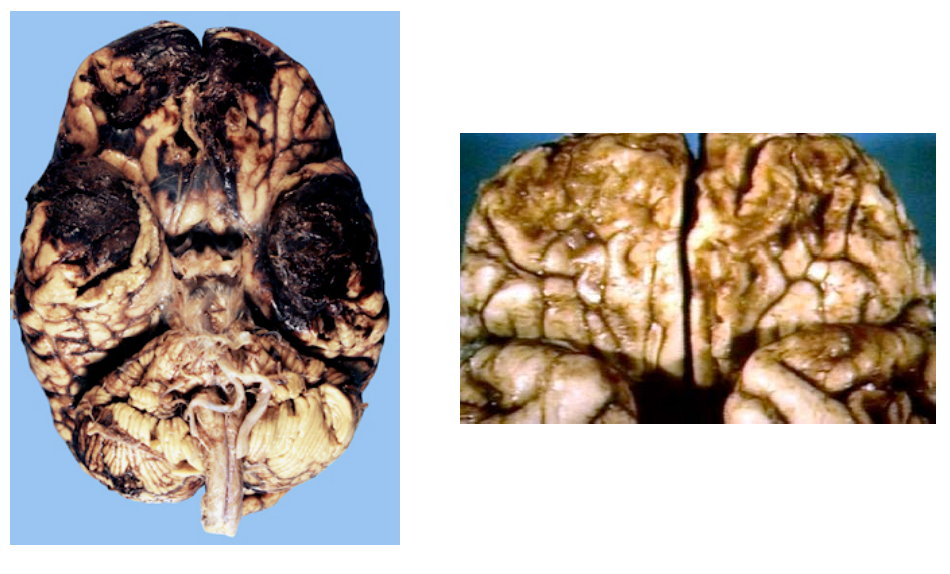

What type of stroke caused this? What is the underlying vascular problem identified on pathology?

Lacunar infarction

• Infarctions ranging in size from 1 mm to 1.5 cm (arrow)

• Classically, the walls of small arteries become thickened from the formation of hyalinemembranes (lipohyalinosis) (circle)

– Caused by chronic hypertension

Old guy found down and brought back to life. Died of inability to feed himself. What was the cause?

Watershed infarction. Couldn’t eat due to man in a barrel like weakness and couldn’t get food to his mouth. So sad.

What cells are killed of by transient global hypoperfusion?

Transient shock or cardiopulmonary arrest causes focal ischemic injury to neurons with high metabolic rates:

– Layer 3 and 5 of cortex

– Hippocampus

– Purkinje cells